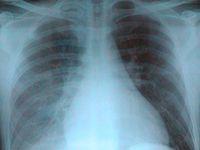

“肺門舞蹈”是一個X線徵象,指在透視下可見兩肺門的粗大肺動脈擴張並有比較明顯的搏動(或肺動脈段和兩側肺門血管搏動增強)。

肺門舞蹈主要見於自左向右分流的先天性心臟病,其產生的原因是:在心室收縮期,有較多的血量沖入肺動脈,使肺動脈在收縮期和舒張期壓力差增大。可見肺門舞蹈這一X線徵象的先天性心臟病有:

(3)在主動脈與肺動脈之間從左向右分流的先天性心臟病,如主、肺動脈間隔缺損及動脈導管未閉。 肺門舞蹈這一X線徵象常見於動脈導管未閉和房間隔缺損。這一徵象也見於某些後天性心臟病如肺心病、二尖瓣心臟病。